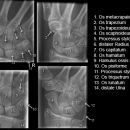

Hand a.p. (dorsovolar)

Beurteilungskriterien

• Kontinuität der drei Karpalbögen (vgl. Handgelenk):

Proximaler Bogen: proximale Gelenkflächenkonturen von Scaphoid, Lunatum und Triquetum

Mittlerer Bogen: distale Gelenkflächenkonturen von Sacphoid, Lunatum und Triquetum

Distaler Bogen: proximale Gelenkflächenkonturen von Capitatum und Hamatum

Fehlende Abgrenzbarkeit, Versatz oder Unterbrechung sind als pathologisch zu bewerten und deuten auf eine Luxation hin.

• M-förmiger Verlauf der Gelenkspalten der Carpometacarpalgelenke? Luxationsstellung in den Carpometacarpalgelenken (meist dorsale Luxation)?

• Gelenkspaltweiten der Carpometacarpalgelenke, der Metacarpophalangealgelenke und Interphalangealgelenke 1 –2mm, der Intercarpalgelenke 1,5 – 2mm

• Täuschungsmöglichkeiten durch Vielzahl akzessorischer Ossikel (abgerundete, zirkulkär-geschlossene Kortikalis), geteilte Handwurzelknochen (Scaphoid, Lunatum, Pisiforme) und Gefäßkanälchen

• Target areas leicht zu übersehender Frakturen:Processus styloideus radii et ulnae, Basen der Metacarpalia (v.a. MCP I) -> großzügige CT-Indikation, Hamulus

Cave: Metacarpale und phalangeale Rotationsfehlstellungen sind konventionell röntgenologisch schwer zu diagnostizieren und zu quantifizieren -> klinischer Befund führend (Fingerstrahl kreuzt bei Beugung im Grundgelenk den benachbarten Strahl), evtl. CT hilfreich.